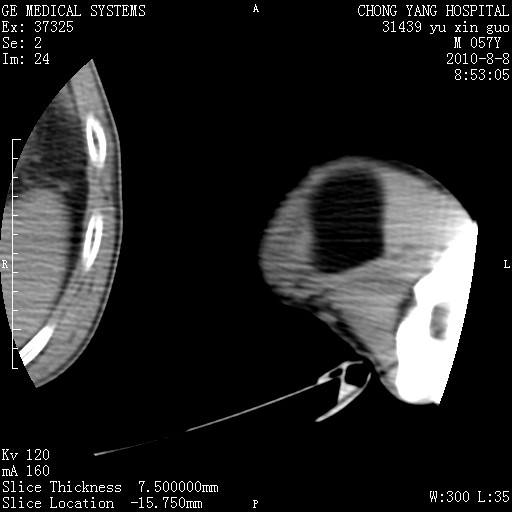

标题: CT28267:M57Y 上臂包块8年余。 [打印本页]

标题: CT28267:M57Y 上臂包块8年余。

典型脂肪瘤改变

包膜光滑、完整的脂肪密度肿块,支持脂肪瘤。